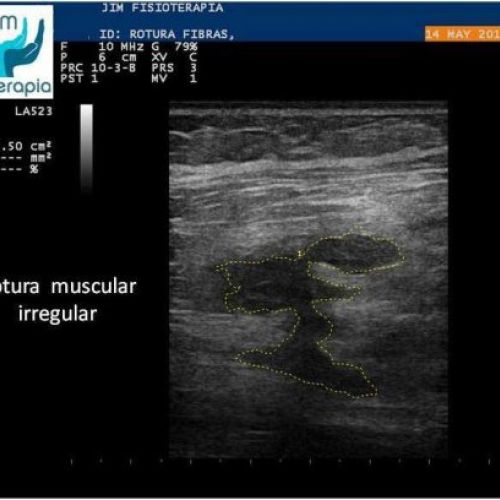

Tratamiento de rotura muscular con EPI®

Terapia de EPI® para el tratamiento de rotura muscular. Caso clínico de JIM Fisioterapia.